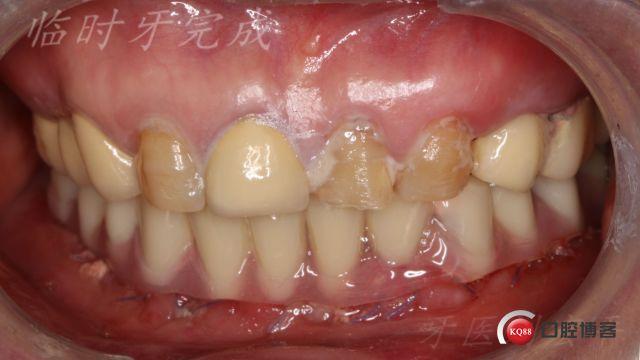

(图片来源网络,侵删)